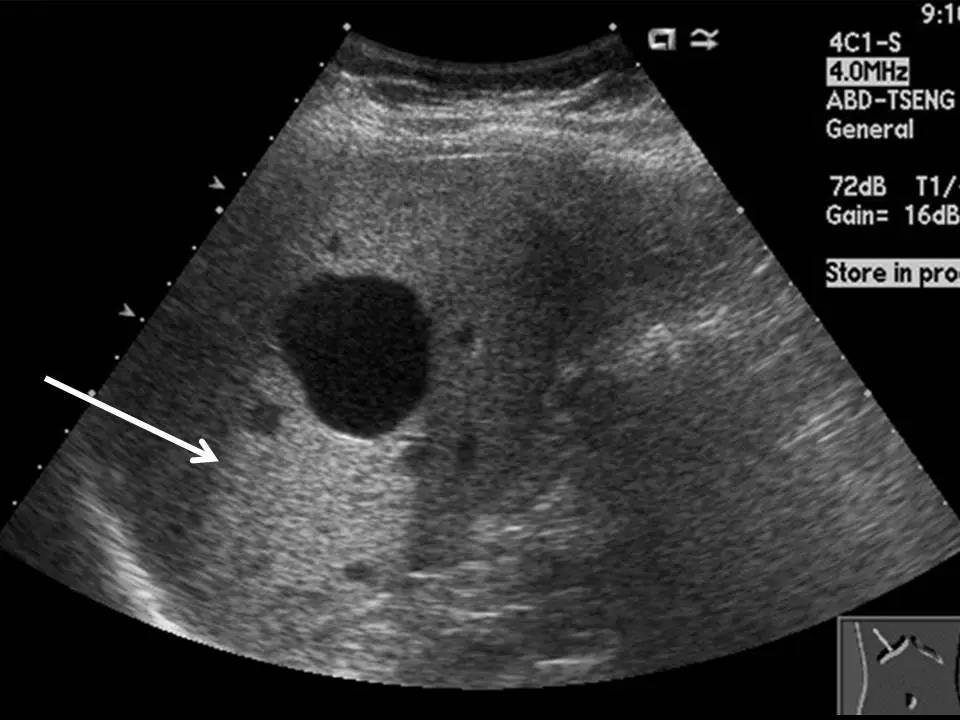

下圖為一肝臟超音波影像,箭號所示之高回音區稱為:

- 主體結構:影像中央偏左可見一個大型、邊界清晰、完全無回音(anechoic)的圓形結構,內部均勻黑色,不含任何實質成分——此為液態結構(fluid-filled structure),最可能為肝臟囊腫(hepatic cyst)或膽囊(gallbladder)。

- 白色箭號所指區域:位於該無回音結構的左後下方(deep/posterior side),出現一條明顯亮白色高回音帶(hyperechoic band),即題目所問之「高回音區」。

- 對照周圍肝實質:箭號所指亮白帶兩側的肝臟實質呈中等回音,而亮白帶正好位於無回音液態結構的正後方,形成鮮明對比——此即「後方回音增強(posterior acoustic enhancement)」的典型影像表現。